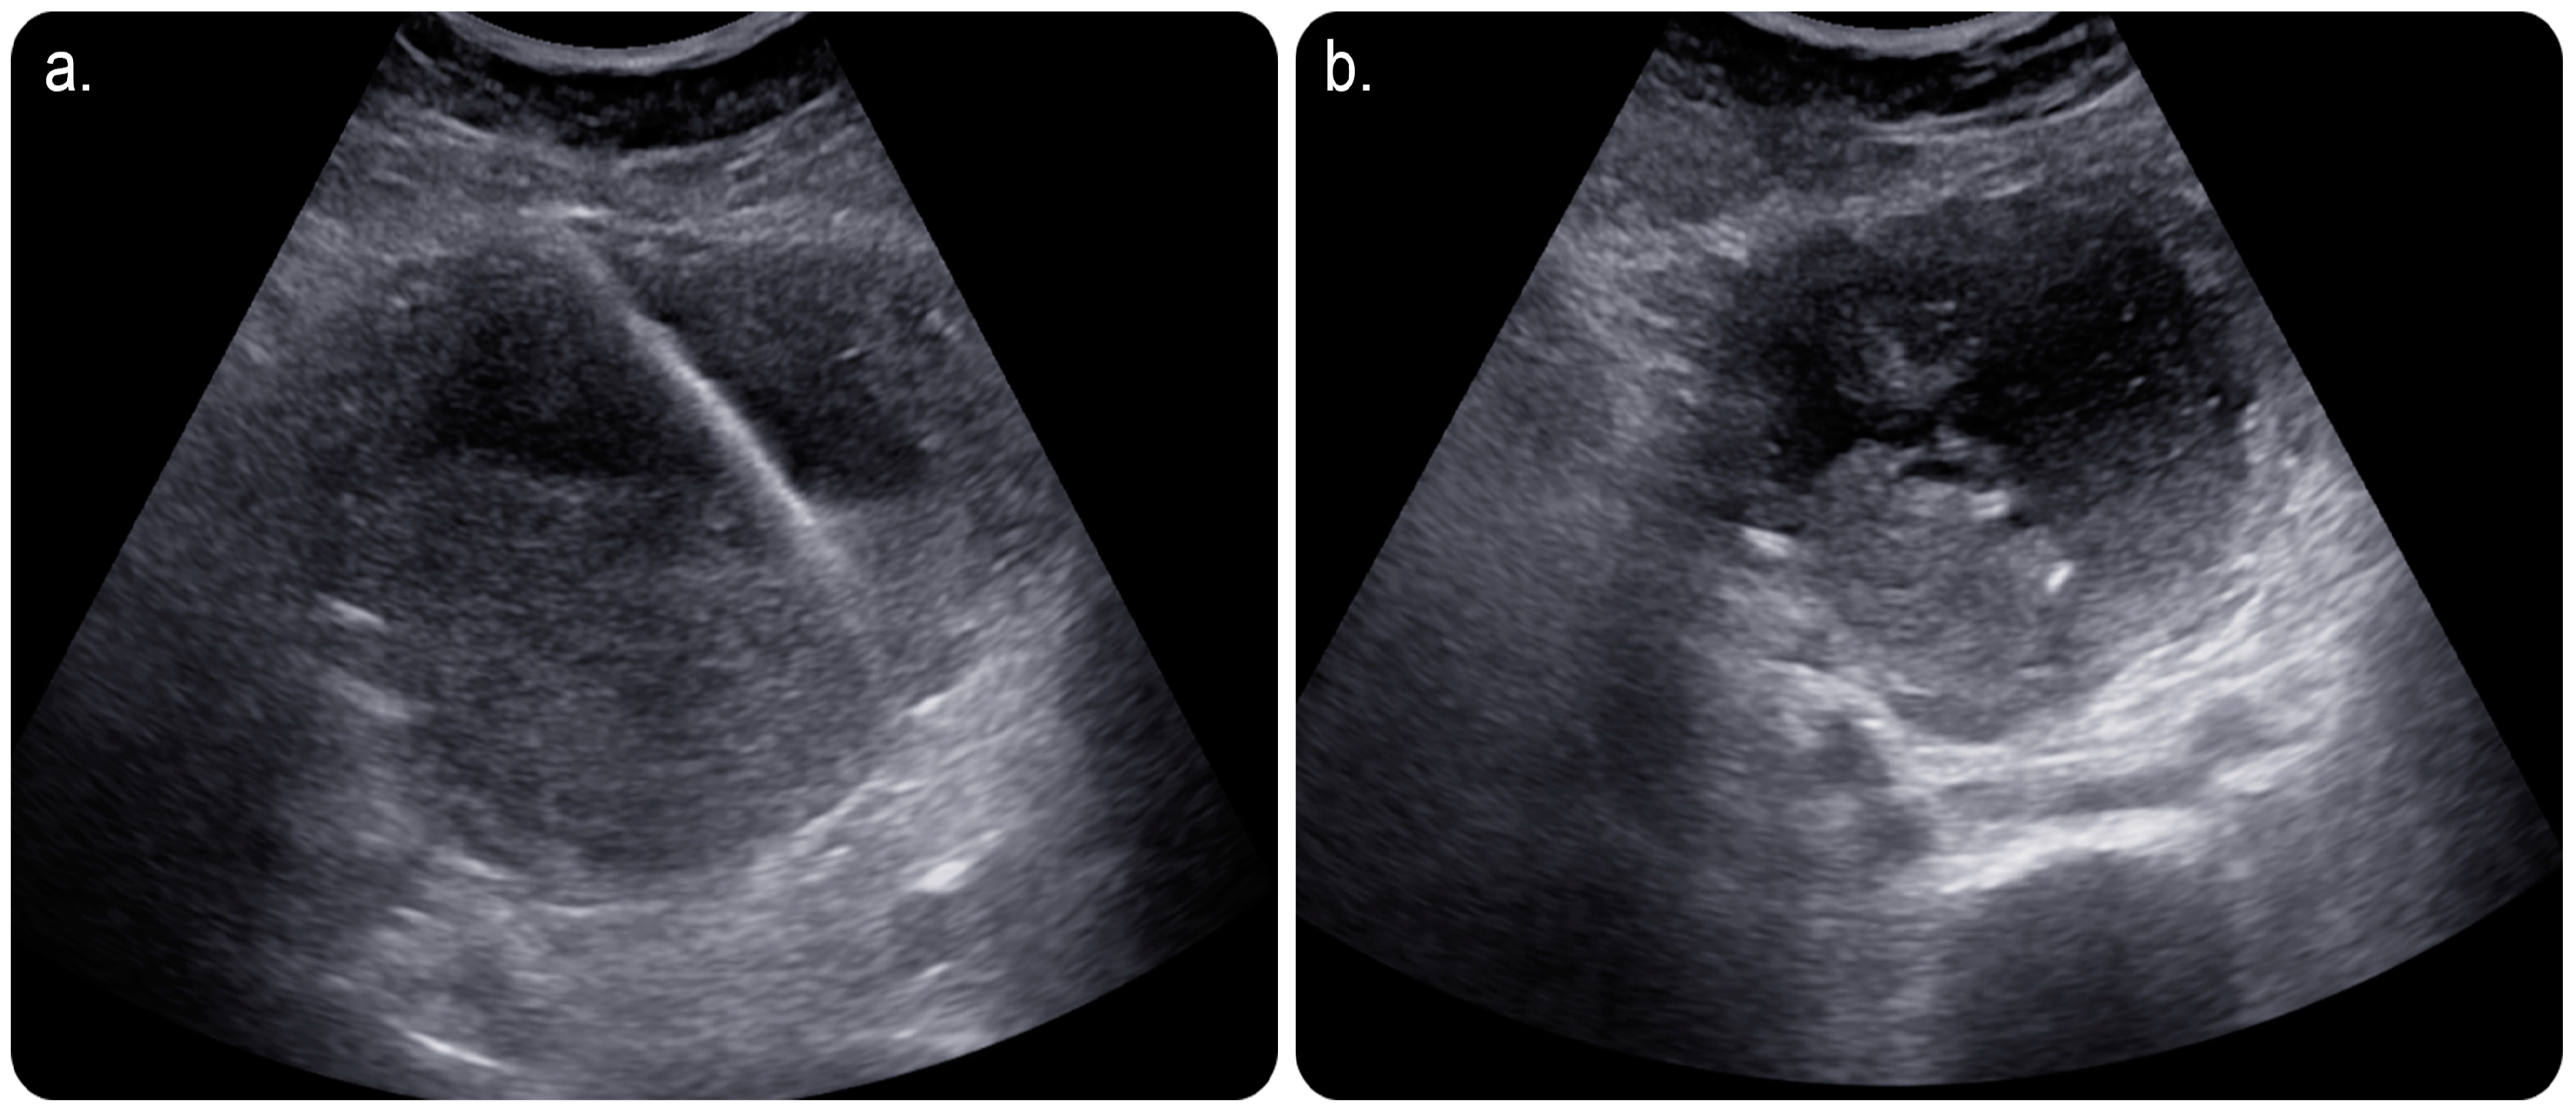

In view of this, the patient was referred to an interventional radiology service for a possible image-guided evacuation of the collection. After obtaining informed consent from the patient and her guardian, we performed an ultrasound-guided percutaneous endometrial drainage of the collection by implementing the dual effects of successive percutaneous retrograde cervical dilation using a non-compliant balloon for stretching the causative cervical stenosis under fluoroscopic guidance; this was followed by retrograde drainage catheter insertion under sonographic guidance in one session (Figure 2 and Figure 3).

Figure 2. (a) Limited grey-scale ultrasound image of the uterus showing a percutaneous echogenic stiff wire inserted through the skin and subcutaneous layers; subsequently, it was secured in the endometrial cavity after an access was obtained using an 18-gauge needle. (b) Grey-scale ultrasound image showing a ring-shaped echogenicity at the dependant portion of the collection representing a 10-French-size pigtail catheter looped within the endometrial cavity.